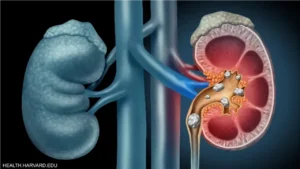

أداة الذكاء الاصطناعي BMVision تسرّع تشخيص سرطان الكلى بنسبة تقليل زمن التحليل إلى الثلث

اكتشاف سرطان الكلى في وقت قياسي أصبح ممكنًا بفضل استخدام أداة ذكاء اصطناعي متقدمة طوّرها باحثون في جامعة تارتو بإستونيا، حيث ساهمت هذه الأداة في تسريع الكشف ...